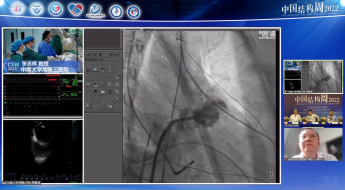

广东省人民医院罗建方教授团队带来一例二尖瓣机械瓣置换术后TAVR手术。由于该患者也存在三尖瓣关闭不全问题,但考虑到右心衰不严重,则优先处理主动脉狭窄问题。术后患者血流动力学稳定,舒张压64mmHg,无瓣周瘘问题。

手术策略:全身麻醉、右股入路、无预扩张、23mm或26mm可回收输送系统。

针对该患者有轻度钙化、瓣环直径21mm,与会专家建议可以预扩,若不行预扩,则先要做好冠脉保护。此外,考虑到患者二尖瓣机械瓣置换术后,本次TAVR手术是否会出现瓣架展开问题,以及是否对机械瓣有影响也是重点关注的内容。对此,参照文献专家建议需注意: